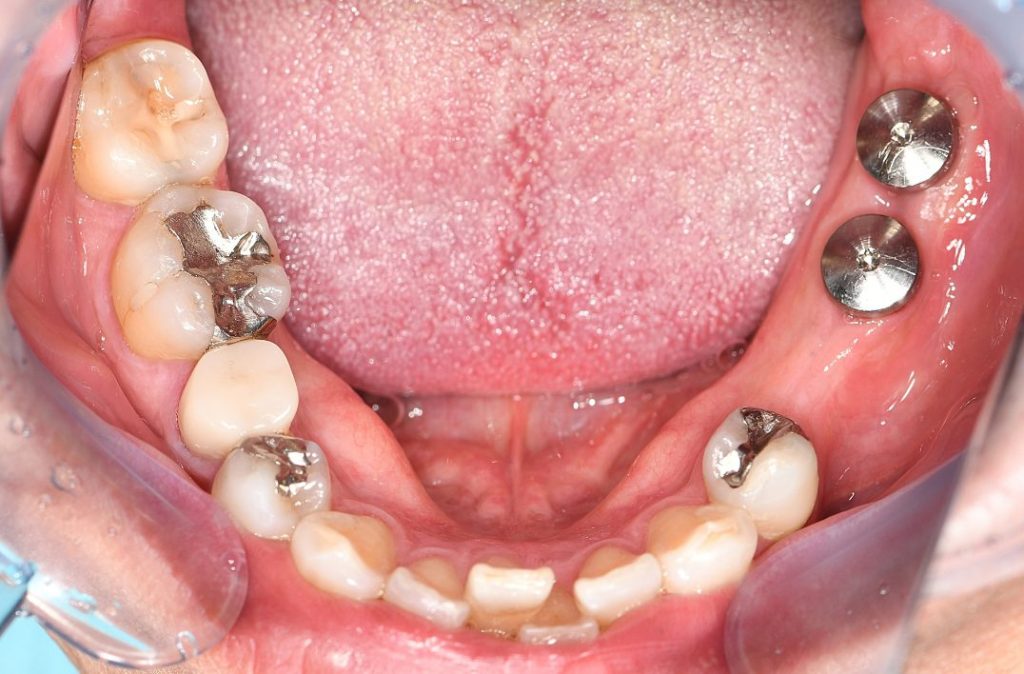

インプラント埋入後

上部構造セット後

左下5番・6番・7番の欠損に対し、咬合力が最も強く集中する左下大臼歯部(6番・7番)に

インプラント治療を実施し、

左下小臼歯部(5番)については、インプラントは埋入せず、奥のインプラントを土台として

歯を前方に“伸ばす”構造(カンチレバー設計)により回復しています。

・最も咬合力が集中する左下6・左下7部位にインプラント2本埋入

・左下5部位はカンチレバー構造を応用し、インプラント本数を最小限に抑制

する設計とした。

抜歯後、治癒期間・インプラント治療工程を経て、

抜歯から約10ヶ月で補綴治療を含めた全治療が終了

現在は、機能的咬合・審美性・清掃性を確保した状態で、良好な経過管理下にある。

術後の経過

インプラント治療が終了してから3ヶ月が経過していますが、ご自宅での清掃も適切に行ってくださっており、定期的なメンテナンスにもしっかりと通ってくださっているので、トラブルなくご使用いただいております。